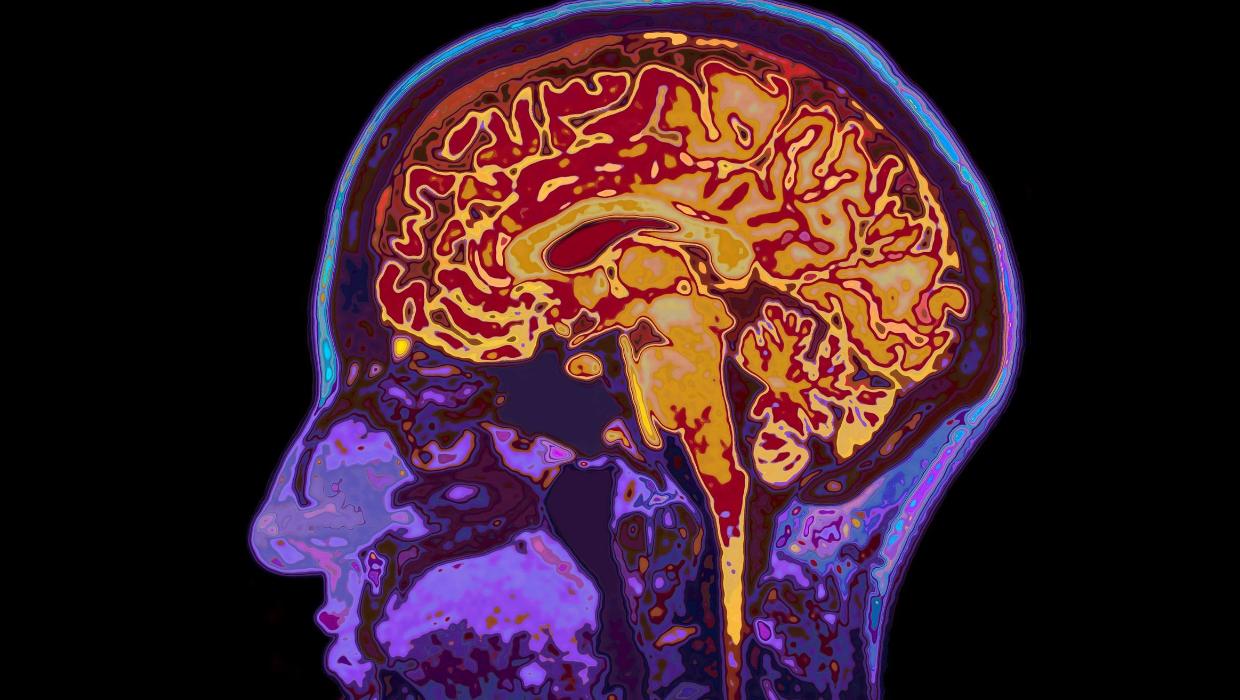

Recent research from the University of Cambridge has revealed that human brain development continues into the early thirties, specifically until the age of 32. This groundbreaking study identifies five major epochs of brain development, highlighting four significant turning points throughout a person’s life.

The study, led by Dr. Camilla Nord, provides valuable insights into how individuals evolve cognitively and emotionally. Researchers utilized advanced imaging techniques to analyze brain scans from over 700 participants aged 5 to 40. The findings indicate that while the brain undergoes substantial changes during childhood and adolescence, it continues to mature well into early adulthood.

The research categorizes brain development into distinct epochs: childhood, adolescence, young adulthood, middle age, and old age. Each epoch is characterized by different cognitive abilities and emotional capacity. According to Dr. Nord, the four turning points are crucial in shaping personality, decision-making, and emotional regulation.

One of the most notable discoveries is that aging begins at 66, a finding that challenges previous assumptions about cognitive decline. The study suggests that individuals may maintain cognitive flexibility and emotional resilience well into their sixties, offering a new perspective on aging.

Dr. Nord emphasizes the implications of these findings for education and mental health. “Understanding that the brain remains plastic and capable of development until age 32 can inform approaches in educational settings, as well as therapeutic practices,” she stated.